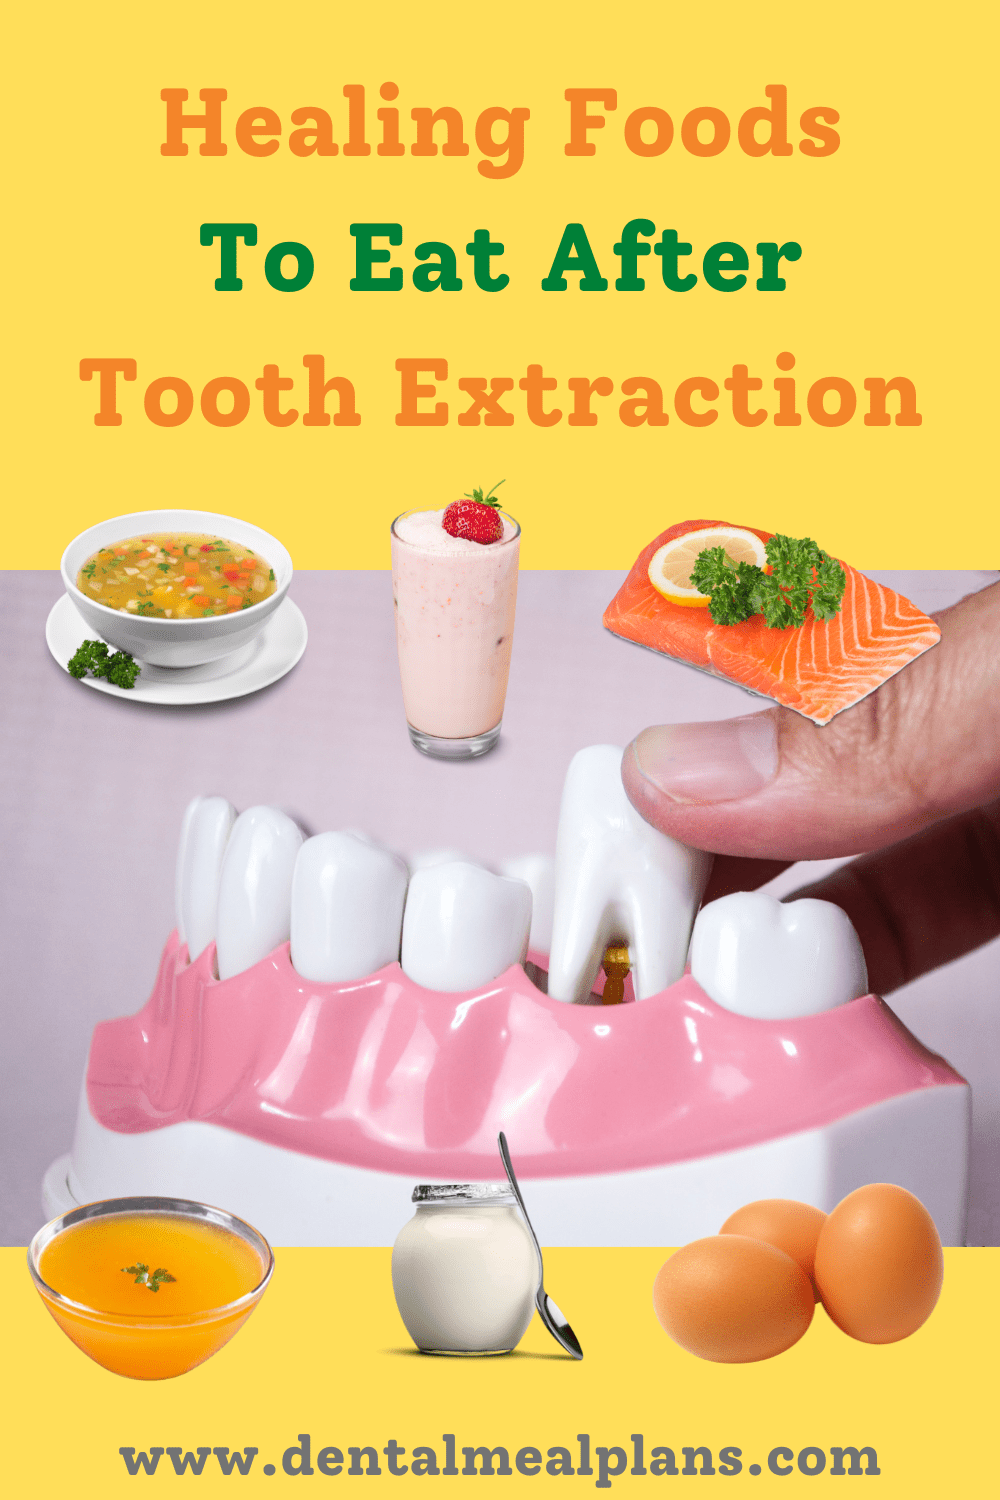

Healing Foods To Eat After Tooth Extraction And A Free Sample Meal

If you ve had a tooth extraction on just one side of your mouth that certainly makes it easier to eat foods but you still need to be careful Keep reading below to learn more about How soon you can eat after tooth Why Focus on the Diet After an Extraction Speeding up the Healing Process A nutrient rich diet can foster cell regeneration and aid in quicker wound healing Reducing the Risk of Infections

Eating soft foods is important for comfort and healing after tooth extraction You can enjoy smoothies scrambled eggs and more The right foods can greatly help your recovery Soft foods are essential after a tooth extraction near you for several key reasons Minimize Discomfort Eating soft foods reduces the need for chewing which minimizes pressure on the extraction site and helps alleviate pain and

After tooth extraction it is generally advisable to gradually transition from soft foods to solid foods rather than immediately switching back to a regular diet This allows the extraction site to heal properly without putting excessive Cold foods can help reduce swelling and numb the area around the extraction site relieving discomfort Few excellent options include smoothies ice cream and yogurt You can also try freezing fruits or vegetables and eating them as a